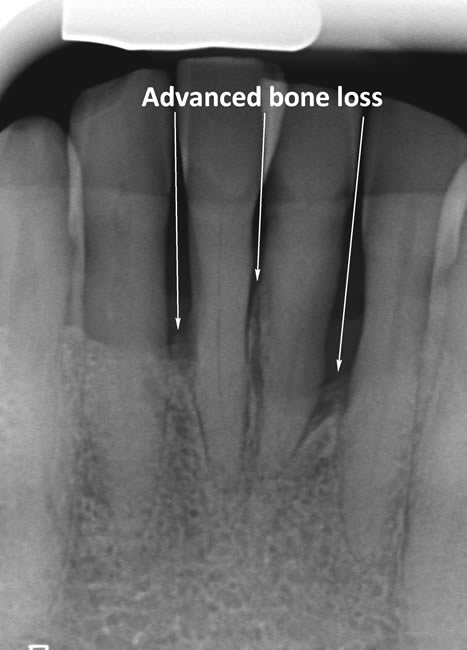

The diagrams below show the different stages of gum disease

Periodontitis is a more advanced stage of gum disease where there has been damage to the bone which supports the teeth. If left untreated periodontitis leads to more and more bone loss until the teeth start to become loose and eventually fall out by themselves or need to be extracted by a Dentist.

The main cause of gum disease is plaque. Plaque consists of millions of bacteria which live on and around the teeth and gums. These bacteria produce toxins which damage the gums. To begin with the gums start to peel away from the teeth and “pockets” form. As the bacteria penetrate deeper into these “pockets” they then start to cause damage to the bone which holds the teeth in. As more bone loss occurs the teeth start to become increasingly looser until they eventually start to fall out one by one.

In cases of advanced gum disease our Hygienist’s will also carry out deep scaling which cleans the root surfaces beneath the gum level. When pockets develop in the gums around the teeth plaque bacteria and calculus form on the root surfaces of the teeth and are protected from toothbrushing by the overlying gum. However, our Hygienist’s have special thin scaling instruments which can go down inside the pockets to clean the root surfaces. This treatment is carried out in small sections under local anaesthetic to ensure that you are comfortable throughout the treatment.